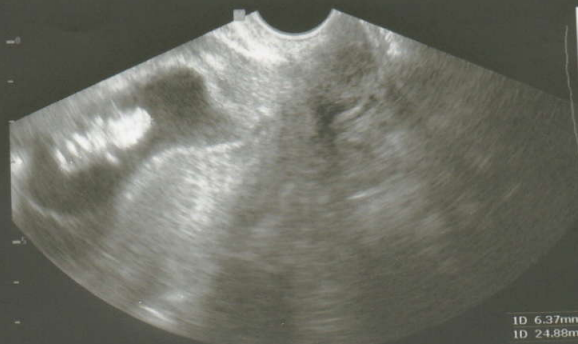

Процесът на ин витро оплождане включва няколко основни стъпки. Първо, жената приема лекарства, които стимулират яйчниците да произвеждат повече яйцеклетки. След това яйцеклетките се изваждат и се смесват с мъжкия материал в лаборатория. След определен период на култивиране, ембрионите се трансферират в матката на жената, където се надява да се постигне бременност.